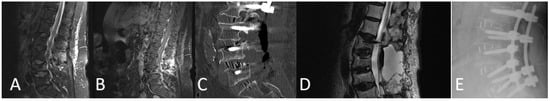

3.10.2. Case 2

A 78-year-old patient with a pathological fracture of Th10 due to breast cancer metastasis underwent multi-stage surgery: RG PS placement at Th8/9-L1/2, followed by implantation of an expandable vertebral body cage via a left transthoracic approach. All screws were GRS A (Figure 21).